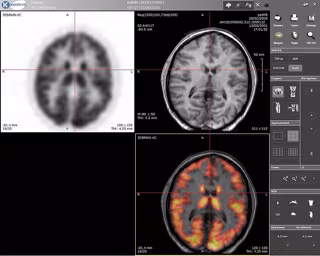

Los científicos, dirigidos por Stanislas Dehaene, utilizaron imágenes de resonancia magnética funcional (IRMf) para escanear el cerebro de 63 portugueses y brasileños que participaban en el estudio y que fueron divididos en tres grupos: adultos que no sabían leer, adultos que aprendieron a hacerlo de niños y adultos que aprendieron a leer de adultos. En contraste, la mayoría de experimentos de neuroimagen en adultos se suelen realizar en estudiantes con una educación elevada.